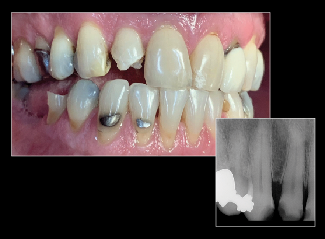

Fig 15. Smartphone dental photography can also be used in laboratory shade communication. In these images taken using MDP, the photo on the left shows value selection, while the one on the right shows chroma/hue selection.

Figure 15